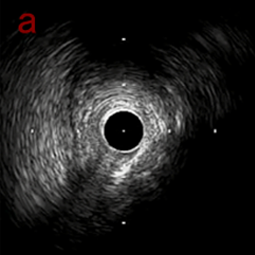

IVUS imaging

IVUSでは8時方向からPD枝がはいいてくる。

PreのIVUSではaの部位のみlipid plaqueを認め削ることでdistal embolismのリスクがあり、そのほかは270度の偏心性石灰化であるがwire biasは良好。